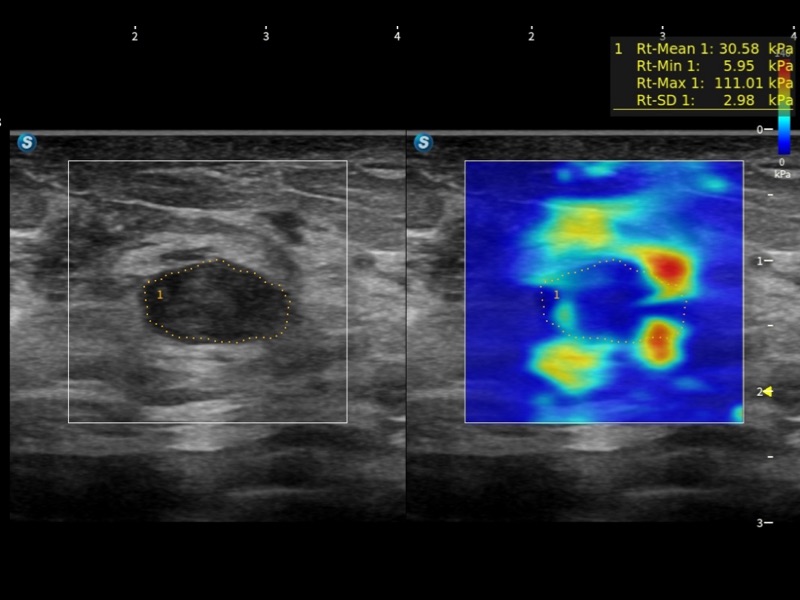

通过光照模型,使二维血流显示出立体的效果,增加血流的敏感性、成束性,减少外溢。可以和其他不同的血流技术联合使用,融合不同技术的优势。轻松应对微小血管,增强血流的立体效果,提升视觉敏感性。